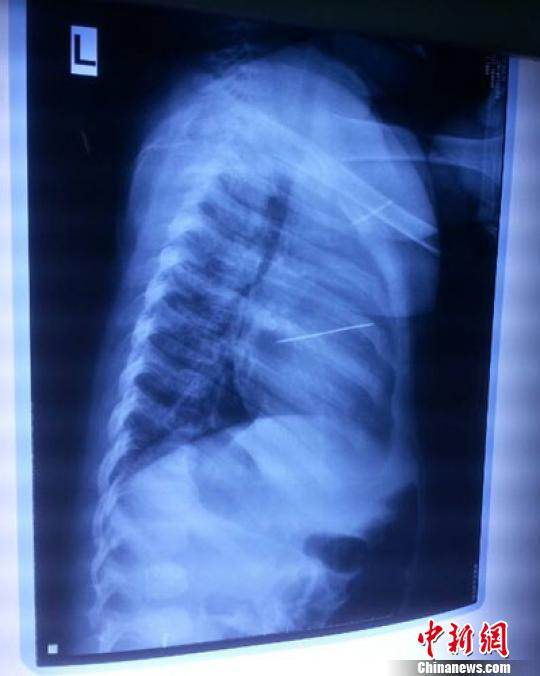

女嬰胸片提示心臟里面扎了一個縫衣針 蔡迅翔 攝

醫(yī)院胸心外科主任翟波介紹說,1月22日,小患者彤彤因為發(fā)燒抽搐來醫(yī)院就診,常規(guī)檢查時發(fā)現(xiàn)孩子心臟里面扎了一個縫衣針。

“第二天上午,我們做了個緊急彩超檢查,發(fā)現(xiàn)針是從患者右心室表面刺入,穿破室間隔,到達左心房,中間還有一部分損害到二尖瓣。于23號下午,我們就做了一個緊急手術(shù),手術(shù)中發(fā)現(xiàn),這枚針已經(jīng)刺入心臟,沒入了右心室的下面,表面已經(jīng)看不到針了,僅能看到一個小針眼,還在往外滲血,一點一點的滲,心包腔里面大概有100多毫升的出血,心包上一個洞,針在右心室表面刺入以后,穿過室間隔,在二尖瓣的上方,進入了左心房,在針的四周,有很多纖維沉積物,包繞著這枚針。”翟波說,他們把針取出來以后,測量了一下,長度大概是五厘米,同時發(fā)現(xiàn)這個針給患者左心房的后壁造成了一定的損傷,左心房的后壁已經(jīng)損傷了三分之二,還剩下有左心房的外膜,很薄的一層,如果這一層再破的話,這個孩子將會引起大出血,很快就會死亡。